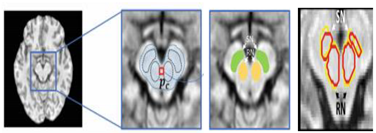

- Atlas: allows an image segmented by an automated algorithm to correspond to a reference image (atlas) [108,109]. These techniques take into account a priori knowledge of brain structures and manage segmentation as a recording problem. They are used in clinical practice, for computer-assisted diagnosis and offer a standard system for detecting properties and morphological differences between patients. They allow segmentation even if there is not a well-defined relationship between the intensities of the pixels and associated regions. However, building an atlas takes time. Difficult to produce objective validation, because segmentation is used when the information from the gray level intensities is not sufficient.